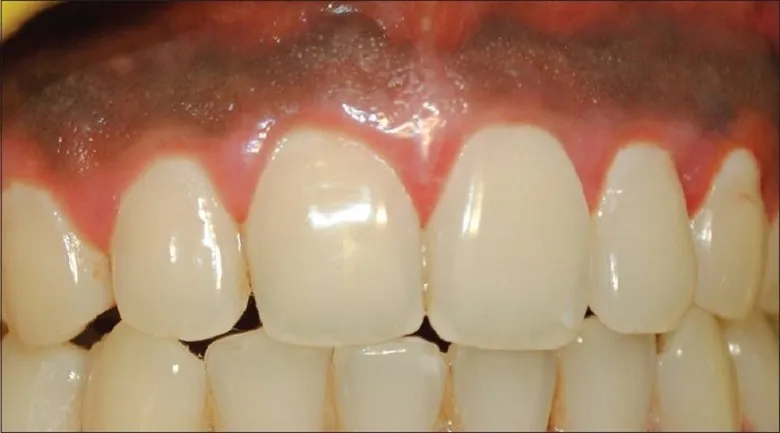

اگر ضخامت بافت لثه کم باشد، رنگ خاکستری یا تیره فلز تیتانیوم میتواند از زیر لثه مشخص شود. این مسئله خطرناک نیست، اما از نظر زیبایی ممکن است برای بیمار ناخوشایند باشد.

| آبی یا خاکستری روشن | تا ۱۴ روز | طبیعی در لثههای نازک | بازتاب رنگ تیتانیوم | نیاز به نگرانی ندارد |

این نوع رنگرفتگی اغلب ناشی از نمایان شدن پایه فلزی ایمپلنت در لثههای نازک است و از نظر پزشکی خطرناک نیست، ولی ممکن است به دلایل زیبایی نیاز به درمان با پیوند لثه داشته باشد.